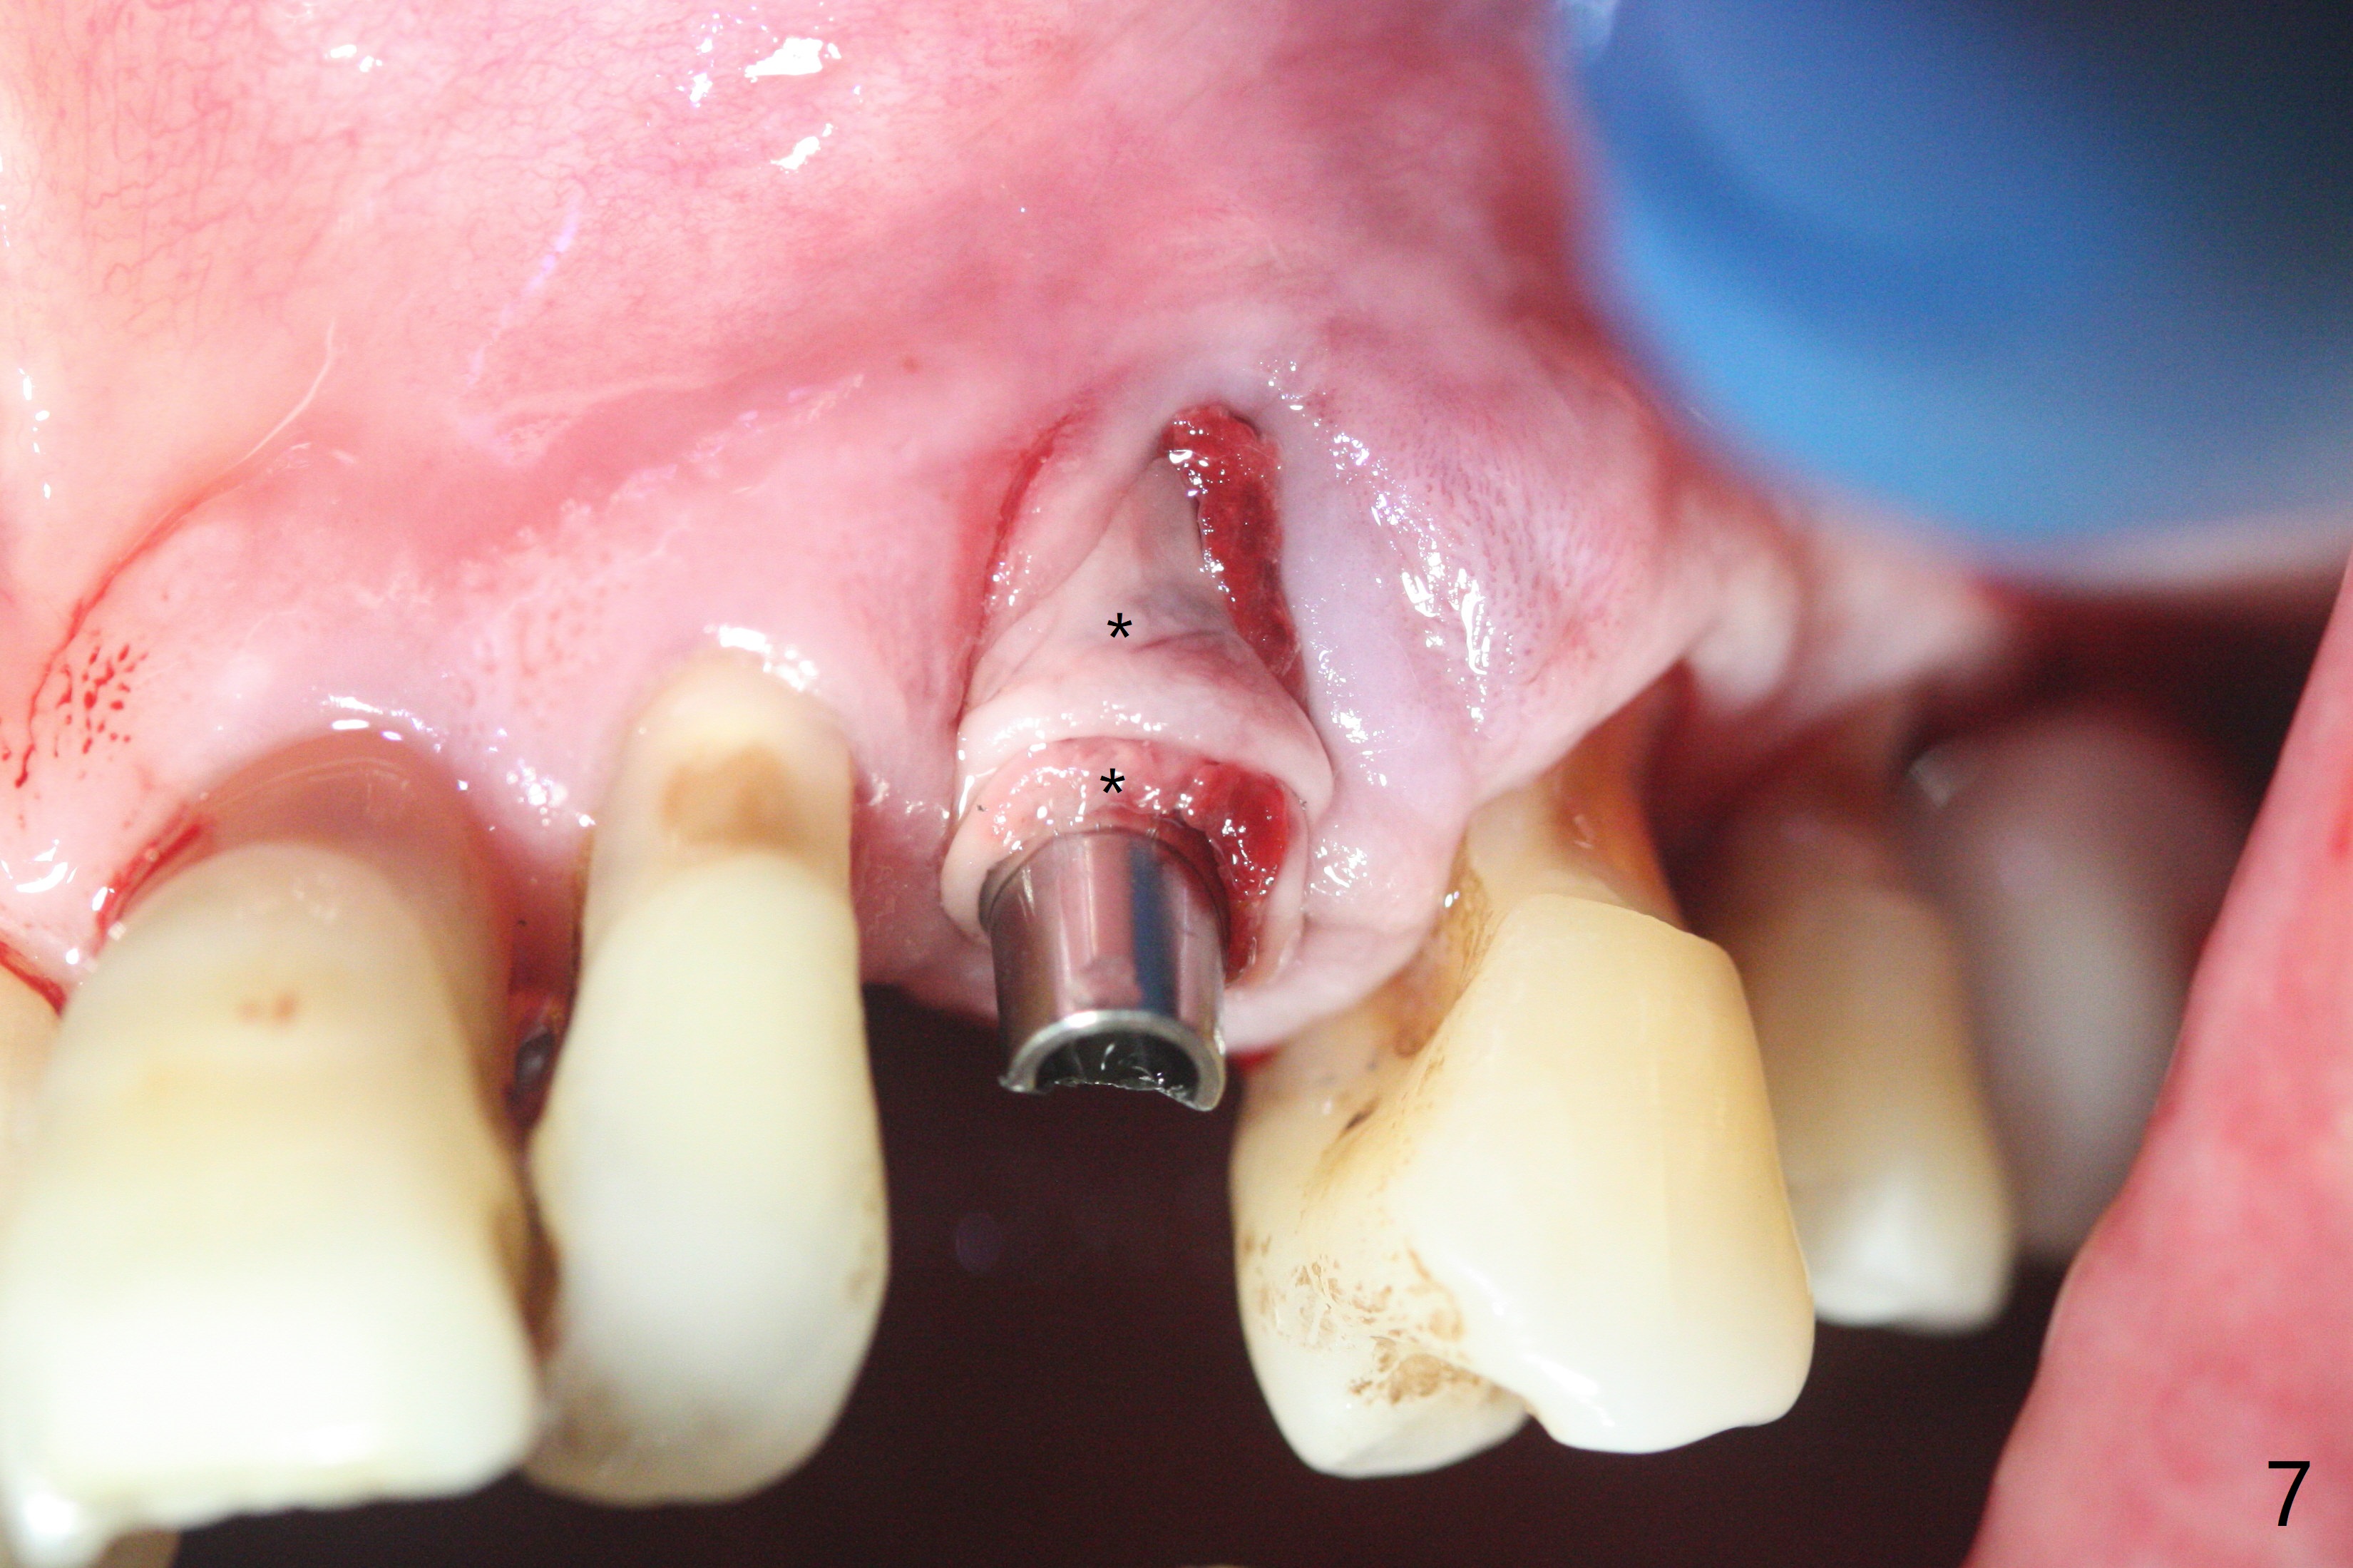

A 62-year-old man with generalized chronic periodontitis returns with chief complaint of loose tooth at #11 (Fig.1). Although a buccal fistula (Fig.1 <) is closer to #12 than to #11, percussion is more severe at #11 than 12. The buccal plate of #11 is missing, but it is possible to place a narrow immediate implant because of the wide alveolus (Fig.2). Since the gingiva is ~ 10 mm long, a mill abutment is to be used (Fig.3,5). In fact the fistula communicates with #11 extraction socket. After debridement, osteotomy is initiated (Fig.4) for a 3.8x10 mm implant ~ 35 Ncm, followed by seating a 4.5x2 mm mill abutment (Fig.5). Abundant sticky bone is placed in the remaining socket (for buccal plate reconstruction) and against the root surface of the neighboring teeth (Fig. 6 * (#10,12)). Finally 2 pieces of PRF membranes are utilized to facilitate repair of the buccal soft tissue defect (Fig.7 *). The root prominence of the canine seems to be maintained by the bone graft (Fig.8 C). Acrylic dressing holding the PRF membranes in place remains in situ with the healthy gingiva buccal (Fig.9) and palatal (Fig.10) 11 days postop. Note the acrylic locking into the undercuts of the neighboring teeth (*). 经过一段摸索发现离心每分钟1500转5分钟后,抽取上清液,接着再离心10分钟剩余上清液就形成血小板块,压制后便是血小板膜,后者似乎有助于软组织愈合,而上清液用来制备骨块,帮助硬组织生长。利用这个原则讨论以下病例治疗。The gingival margin gains ~ 5 mm 6 weeks postop when the acrylic dressing is removed (Fig.11,12 (<: previous one), as compared to Fig.7,8). 治疗结束时尖牙牙龈缘高于第一双尖牙(图七,八),六个星期后,尖牙牙龈缘却低于双尖牙(图十一,十二(箭头:原始牙龈缘))。术后2.5,4.5月基台周围牙龈似乎能与钛合金附着,防止细菌进入深部植体(图十三,十四)。临时牙冠脱落多次,可能与mill abutment太光滑有关,所以颊侧,舌侧磨成平面(图十四)。取模时好像不必取出基台清洗(仿佛没有炎症),原位用树脂延长基台。术后5个月CT显示颊侧骨板再生(图十六-十八)。取模时并没有用树脂加长基台;粘固时,牙冠颜色理想,但是照片中并不是如此(图十九,二十),颊侧骨板没有塌陷。术后11个月基台颊侧骨板没有萎缩(图二十一:B);3d图像:骨壁完全形成(图十六对比:部分形成)。密度也增高(图二十二:B),与术后五个月比较(图十七)。术后十一个月,粘固后五个月角化龈存在(图二十三),牙冠颈部有金属颜色透出,是因为二段式基台太粗了(最细4.5毫米),可以请实验室在牙冠内部涂opaque material而减轻。